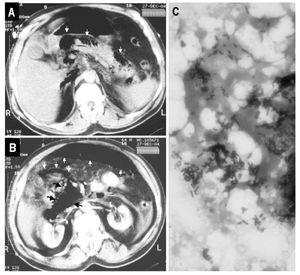

Varón hipertenso de 64 años que acude al hospital por dolor epigástrico de 24 horas de evolución y náuseas. La presión arterial era de 105/85 mmHg, la frecuencia cardíaca de 156 latidos por minuto y la temperatura de 40 ºC. La exploración física puso de manifiesto una deshidratación intensa, mala perfusión periférica y un abdomen doloroso, defendido, timpanizado, sin peristaltismo y con livideces en flancos. En la analítica destacó: glucosa 250 mg/dl, amilasa 1.459 U/l, sodio 140 mEq/l, potasio 4,5 mEq/l, creatinina 1,90 mg/dl, urea 40 mg/dl, creatinquinasa 156 U/l, aminotransferasa de alanina 161 U/l, aminotransferasa aspártica 216 U/l, leucocitos 12,9 x 109/l con 87% neutrófilos, hemoglobina 22,8 g/dl, hematocrito 66% y plaquetas 296 x 109/l. Una gasometría arterial (fracción inspiratoria de oxígeno [FiO2] de 0,31) reveló: pH de 7,37, presión arterial de oxígeno de 63 mmHg, presión arterial de anhídrido carbónico de 22,5 mmHg y bicarbonato de 13,3 mEq/l. El paciente fue tratado con fluidos e imipenen. Una tomografía computarizada (TC) abdominal con contraste mostró necrosis pancreática con gas rodeando el cuerpo y cola del páncreas (fig. 1A) y aire libre intraperitoneal y en el espacio pararrenal anterior derecho (fig. 1B). Ante la sospecha de pancreatitis gangrenosa asociada a perforación de víscera hueca (duodeno), se realizó una laparotomía exploradora que reveló crepitación y olor nauseabundo al abrir la cavidad abdominal, signos de pancreatitis necrohemorrágica y, tras una extensa revisión de la cavidad abdominal, ausencia de perforación intestinal. Se realizó una necrosectomía pancreática y se tomaron muestras para cultivos y tinción de Gram, la cual mostró bacilos grampositivos (fig. 1C). El paciente falleció por shock séptico a las pocas horas de la intervención. En los cultivos se aisló un Clostridium perfringens.

Figura 1. Una tomografía computarizada abdominal con contraste muestra la presencia de gas en cuerpo y cola del páncreas (flechas blancas) (A) y aire libre intraperitoneal (flechas blancas) y retroperitoneal (flechas negras) (B). Tinción de Gram revelando bacilos grampositivos (C).